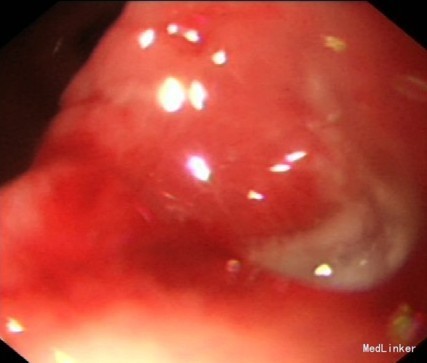

患者男性,75岁,因“反复上腹隐痛一年余,突发腹部疼痛伴腹胀一天”入院 患者一年前出现反复上腹隐痛,3月前于我院门诊就诊,予查胃镜提示(见图一):胃窦溃疡(A1期),活检提示未见癌,予抑酸、护胃治疗后症状有所缓解,病人未按要求及时复诊复查胃镜。一天前患者再发腹痛并腹胀入院。